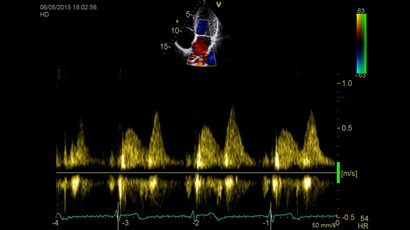

GE VIVID IQ - это передовая портативная система ультразвуковой диагностики, специально разработанная для обеспечения высокого качества образов и мобильности. Благодаря своим компактным размерам и легкому весу, VIVID IQ легко переносится и позволяет проводить УЗИ исследования в различных местах, включая комнаты пациентов, отделения скорой помощи и операционные.

GE VIVID IQ – это ультрасовременный, выполненный в виде ноутбука УЗИ сканер с самым передовым техническим оснащением для проведения диагностических обследований сердечно-сосудистой системы человека. Его особенно оценят бригады скорой помощи из-за малого веса всего 4,5 кг., удобства переноски, а также быстрого выхода из состояния сна для начала работ.

• Передовые технологии, такие как 4D чреспищеводная эхокардиография, ЭКГ, стресс-эхо, внутрисердечная ультразвуковая эхокардиография, тканевый доплер и другие.

Тканевой допплер:

Да

Направленный энергетический допплер:

Энергетический допплер:

Высокочастотный импульсный допплер:

Цветовой допплер:

Постоянно-волновой допплер:

Импульсно-волновой допплер: